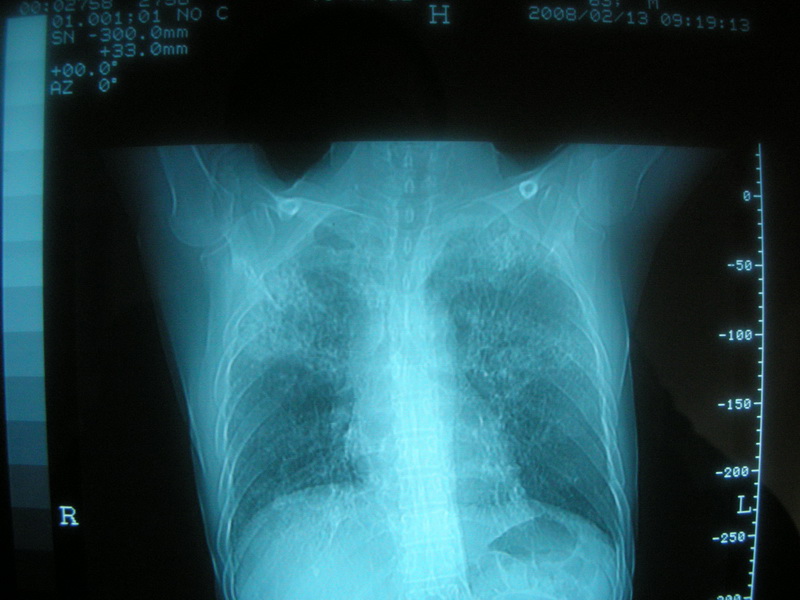

标题: CT11692:男,63岁,糖尿病史15年.抗炎治疗7天,病情 [打印本页]

标题: CT11692:男,63岁,糖尿病史15年.抗炎治疗7天,病情

请老师看看是结核还是炎症?

双肺继发性肺结核伴感染!

双肺继发性肺结核伴支气管播散。